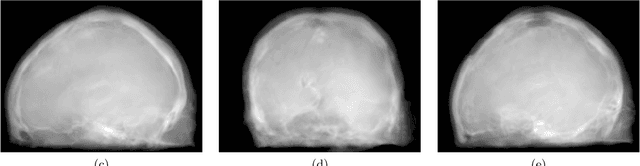

Abstract:Hybrid imaging promises large potential in medical imaging applications. To fully utilize the possibilities of corresponding information from different modalities, the information must be transferable between the domains. In radiation therapy planning, existing methods make use of reconstructed 3D magnetic resonance imaging data to synthesize corresponding X-ray attenuation maps. In contrast, for fluoroscopic procedures only line integral data, i.e., 2D projection images, are present. The question arises which approaches could potentially be used for this MR to X-ray projection image-to-image translation. We examine three network architectures and two loss-functions regarding their suitability as generator networks for this task. All generators proved to yield suitable results for this task. A cascaded refinement network paired with a perceptual-loss function achieved the best qualitative results in our evaluation. The perceptual-loss showed to be able to preserve most of the high-frequency details in the projection images and, thus, is recommended for the underlying task and similar problems.